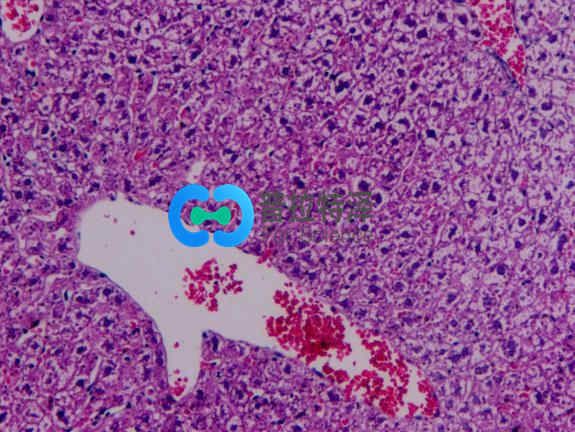

光鏡觀察:

正常組肝小結(jié)構(gòu)正常,肝細(xì)胞以中央靜脈為中心呈放射狀排列。無肝細(xì)胞腫脹及脂肪變性。模型組肝組織HE染色顯示:造模4周后大鼠肝臟即有輕微的肝細(xì)胞脂肪變性,標(biāo)本還出現(xiàn)匯管區(qū)及小葉內(nèi)炎癥細(xì)胞浸潤(rùn)和散在的點(diǎn)狀壞死;造模8周大鼠多呈中度脂肪變,且炎癥活動(dòng)積分明顯高于造模4~8 周大鼠,可見到小葉內(nèi)炎癥,炎癥細(xì)胞主要以單核細(xì)胞為主,炎癥程度明顯加重;造模 18周大鼠呈中重度的大泡性脂肪變,脂滴分布密度通大,可見大部分旺細(xì)胞漿含大脂滴,部分脂滴形成大空泡。將細(xì)胞核擠壓至一邊,目以中央靜脈周圍為其:肝小葉結(jié)構(gòu)破壞,肝細(xì)胞排列不規(guī)救,并伴大量肝細(xì)胞腫脹,部分呈氣球樣變,匯管區(qū)炎癥尚輕微。